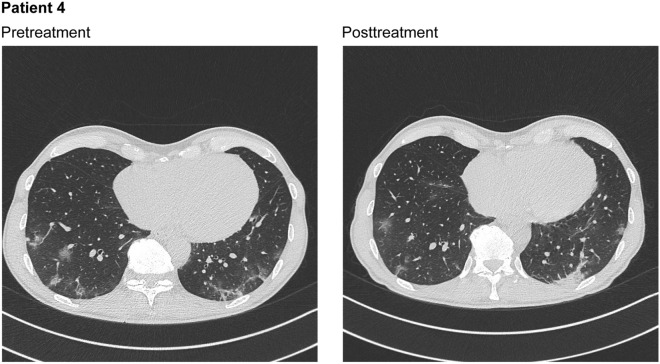

A chest CT scan without contrast that was performed on the day of hospital admission (October 29, 2020) showed parenchymal thickening and multiple associated ground glass areas with crazy paving aspects, predominantly at the basal pyramid of both lower lobes (involving approximately 10% of the lung parenchyma) and small mediastinal lymph nodes (Fig. 4; Table 2). The patient was enrolled in the compassionate use study and treated with nebulized ribavirin from October 30 through November 3. The patient requested hospital discharge on November 3 for family reasons and, therefore, received 10 of the planned 12 doses. The patient was apyretic after the first 2 days of ribavirin therapy, and the cough subsided.

Fig. 4.

Chest computed tomography scans without contrast for patient 4 at pretreatment, showing parenchymal thickening and multiple associated ground glass areas with crazy paving aspects, predominantly at the basal pyramid of both lower lobes, and posttreatment after 5 days of therapy with ribavirin solution for inhalation, showing a stationary pulmonary picture

A chest CT scan performed on the fifth day of ribavirin aerosol therapy (November 3) showed a stationary pulmonary picture with parenchymal involvement of less than 10% (Fig. 4). The patient was discharged from the hospital on November 3; at discharge, a nasopharyngeal swab tested positive for SARS-CoV-2. A follow-up nasopharyngeal swab for SARS-CoV-2 that was performed on November 17 (end of quarantine) yielded negative results.